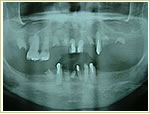

症例1 32歳 男性 画像拡大

治療前 治療後